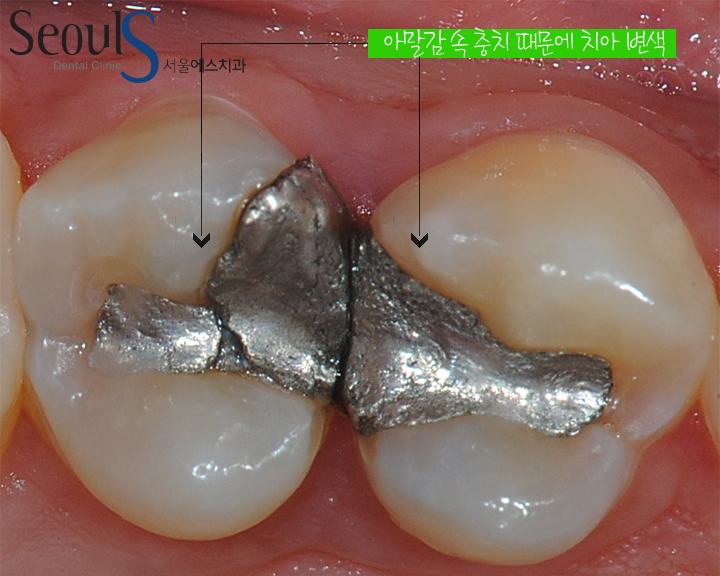

아말감에 틈이 생겼고 그 틈으로 음식물이 들어가 충치가 진행되고 있는 상태입니다

치아를 자세히 보시면

아말감 속으로 충치가 진행되고 있어서 치아 속으로 진행되고 있는 충치가 검게 비춰보입니다